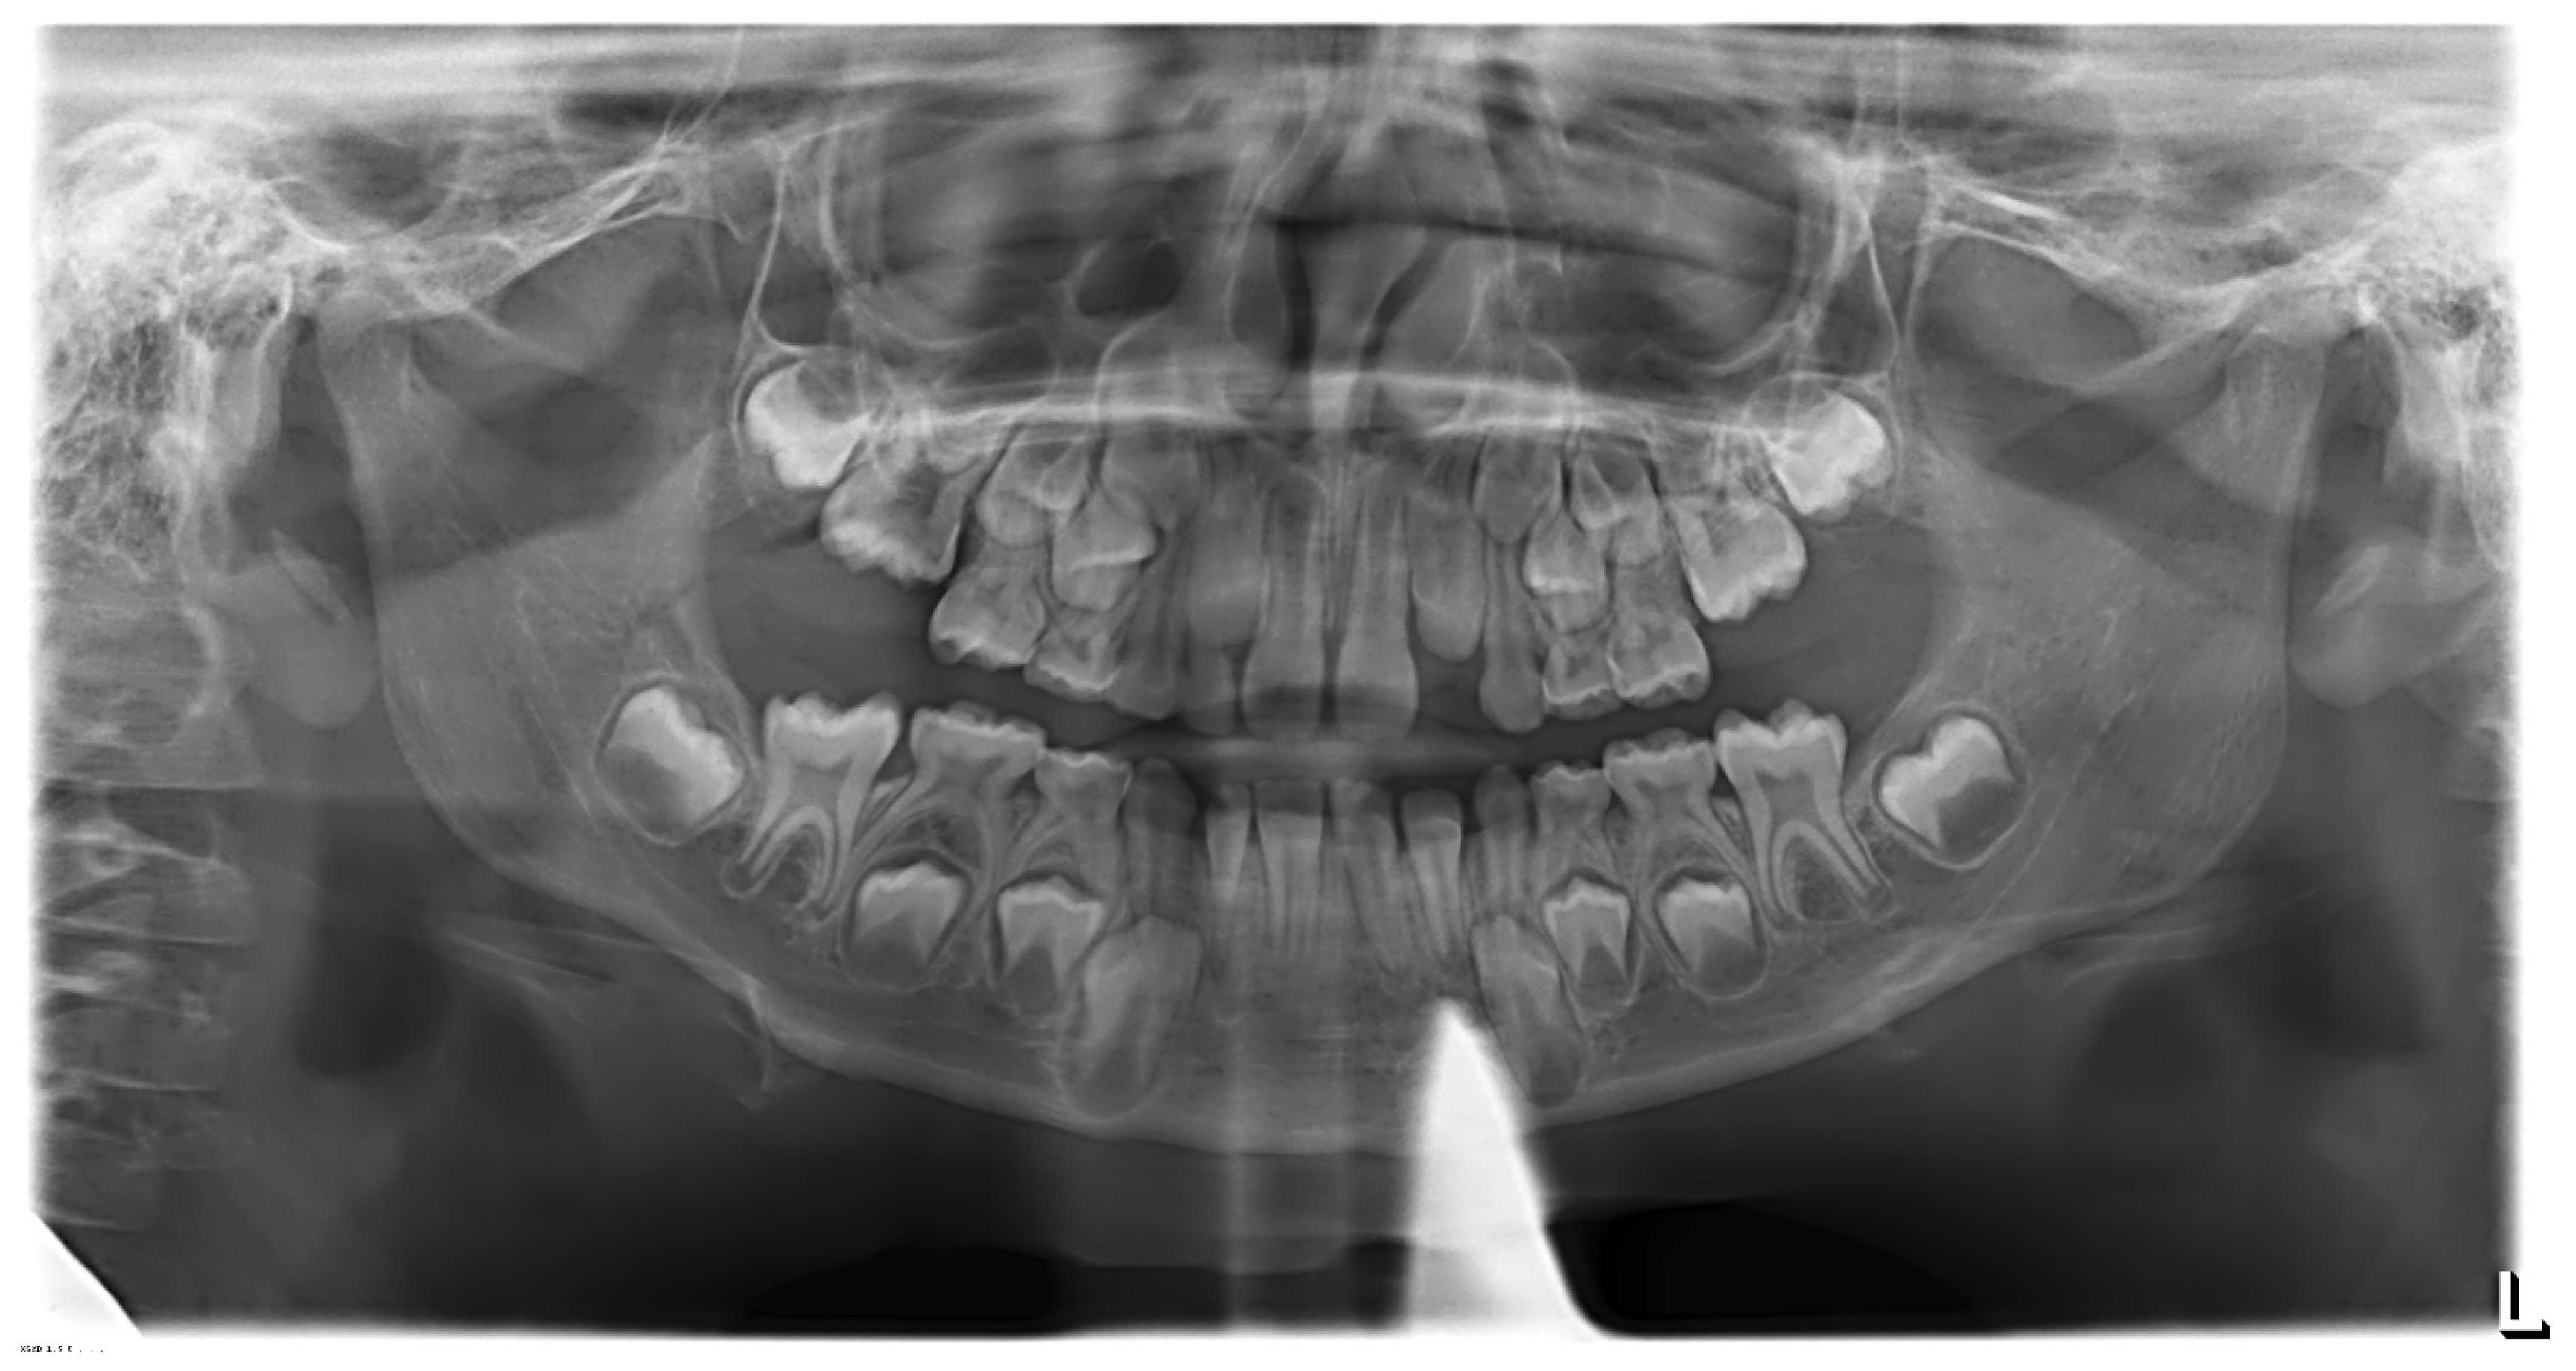

3.2. Clinical Case #2